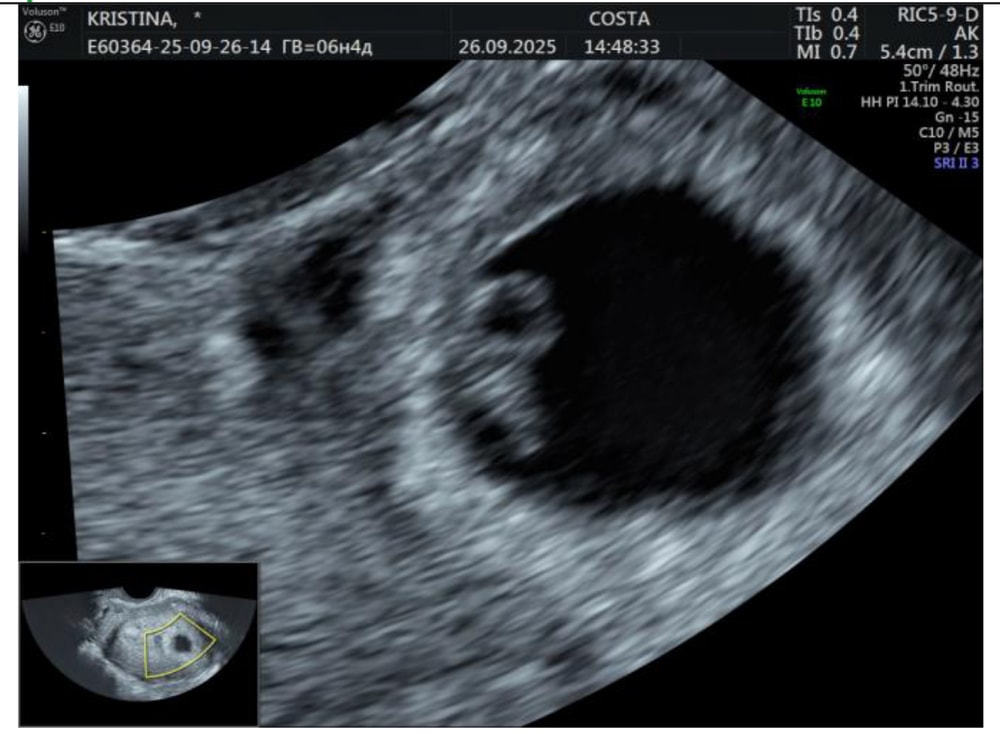

УЗИ.КРЕВЕТОЧКА РАСТЕТ🤞🏻

УЗИ, КТГ, доплерСроки немного разнятся, из за неизвестной овуляции, срок по месячным(в прошлую беременность из за поздней овуляции на приеме в жк изменила день последних мес)кто разбирается, все ок же?) на учет гиня ждёт через 2 недели🙌🏻